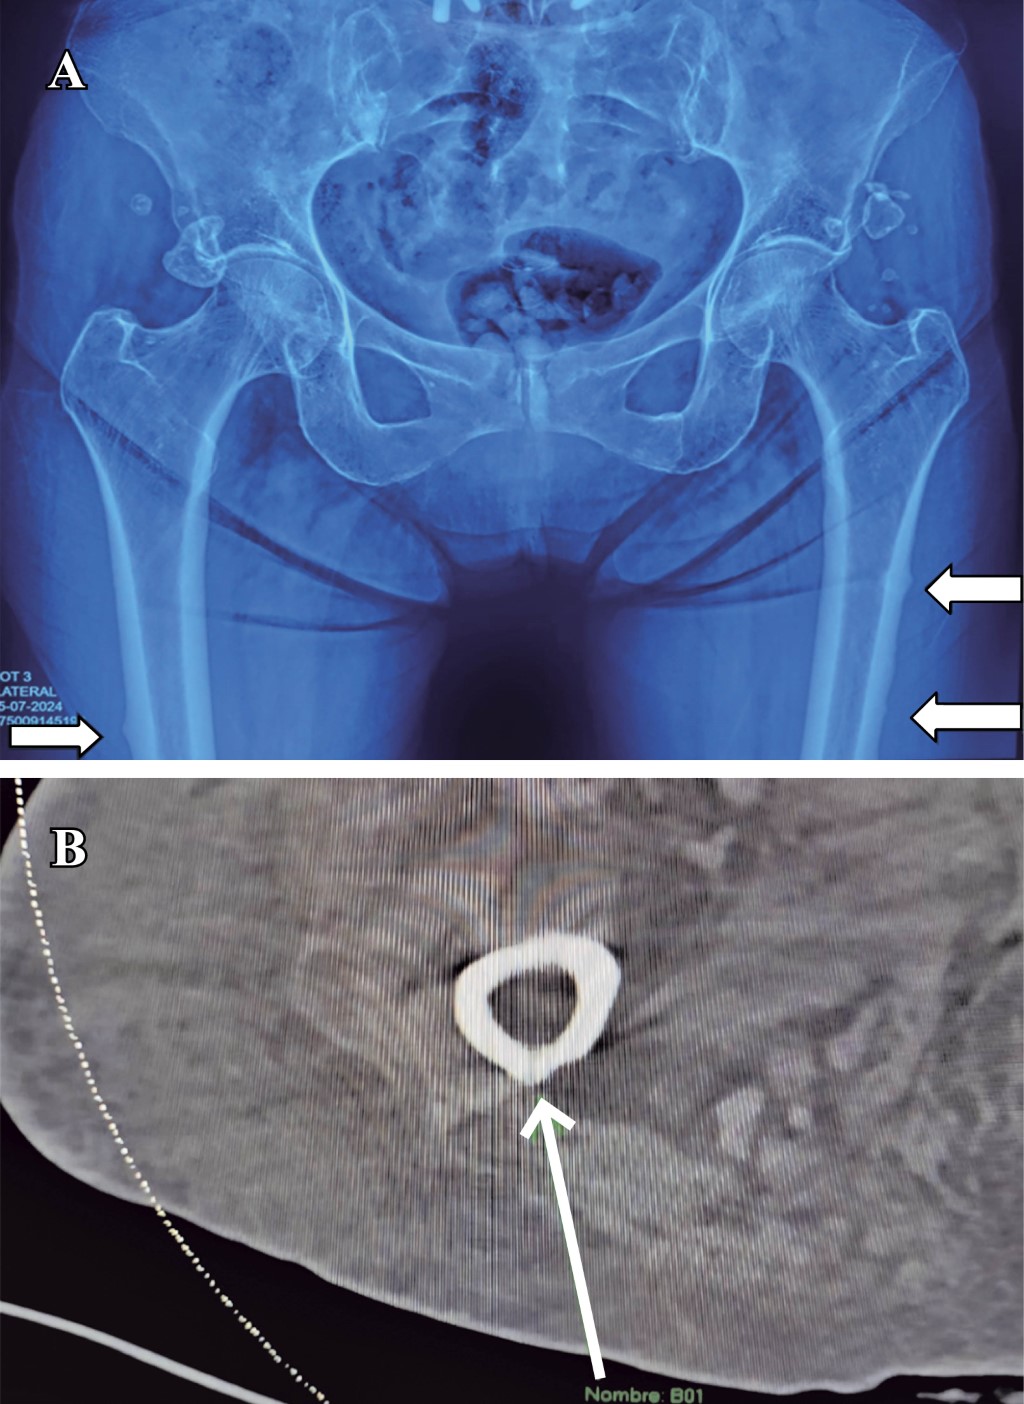

An 83-year-old female with a 10-year history of bisphosphonate treatment for osteoporosis (alendronic acid, 70 mg presentation), came to the orthopedic consult after feeling leg pain. Normal movement, with limitation and instability, while standing up. An X-ray and CT scan of the pelvis were obtained. Figure 1 shows the thickening of the bone cortex, with the presence of atypical incomplete bilateral fractures in the subtrochanteric femur. After a complete assessment, the patient underwent surgical treatment with intramedullary nailing (Figure 2), and thromboprophylaxis with Apixaban 2.5 mg every 12 hours for 28 days was indicated.

After the procedure, bisphosphonate therapy was suspended and replaced with romosozumab, vitamin D, and calcium supplementation. Physical rehabilitation was also prescribed, aiming for gait rehabilitation and full range of motion.

Figure 2